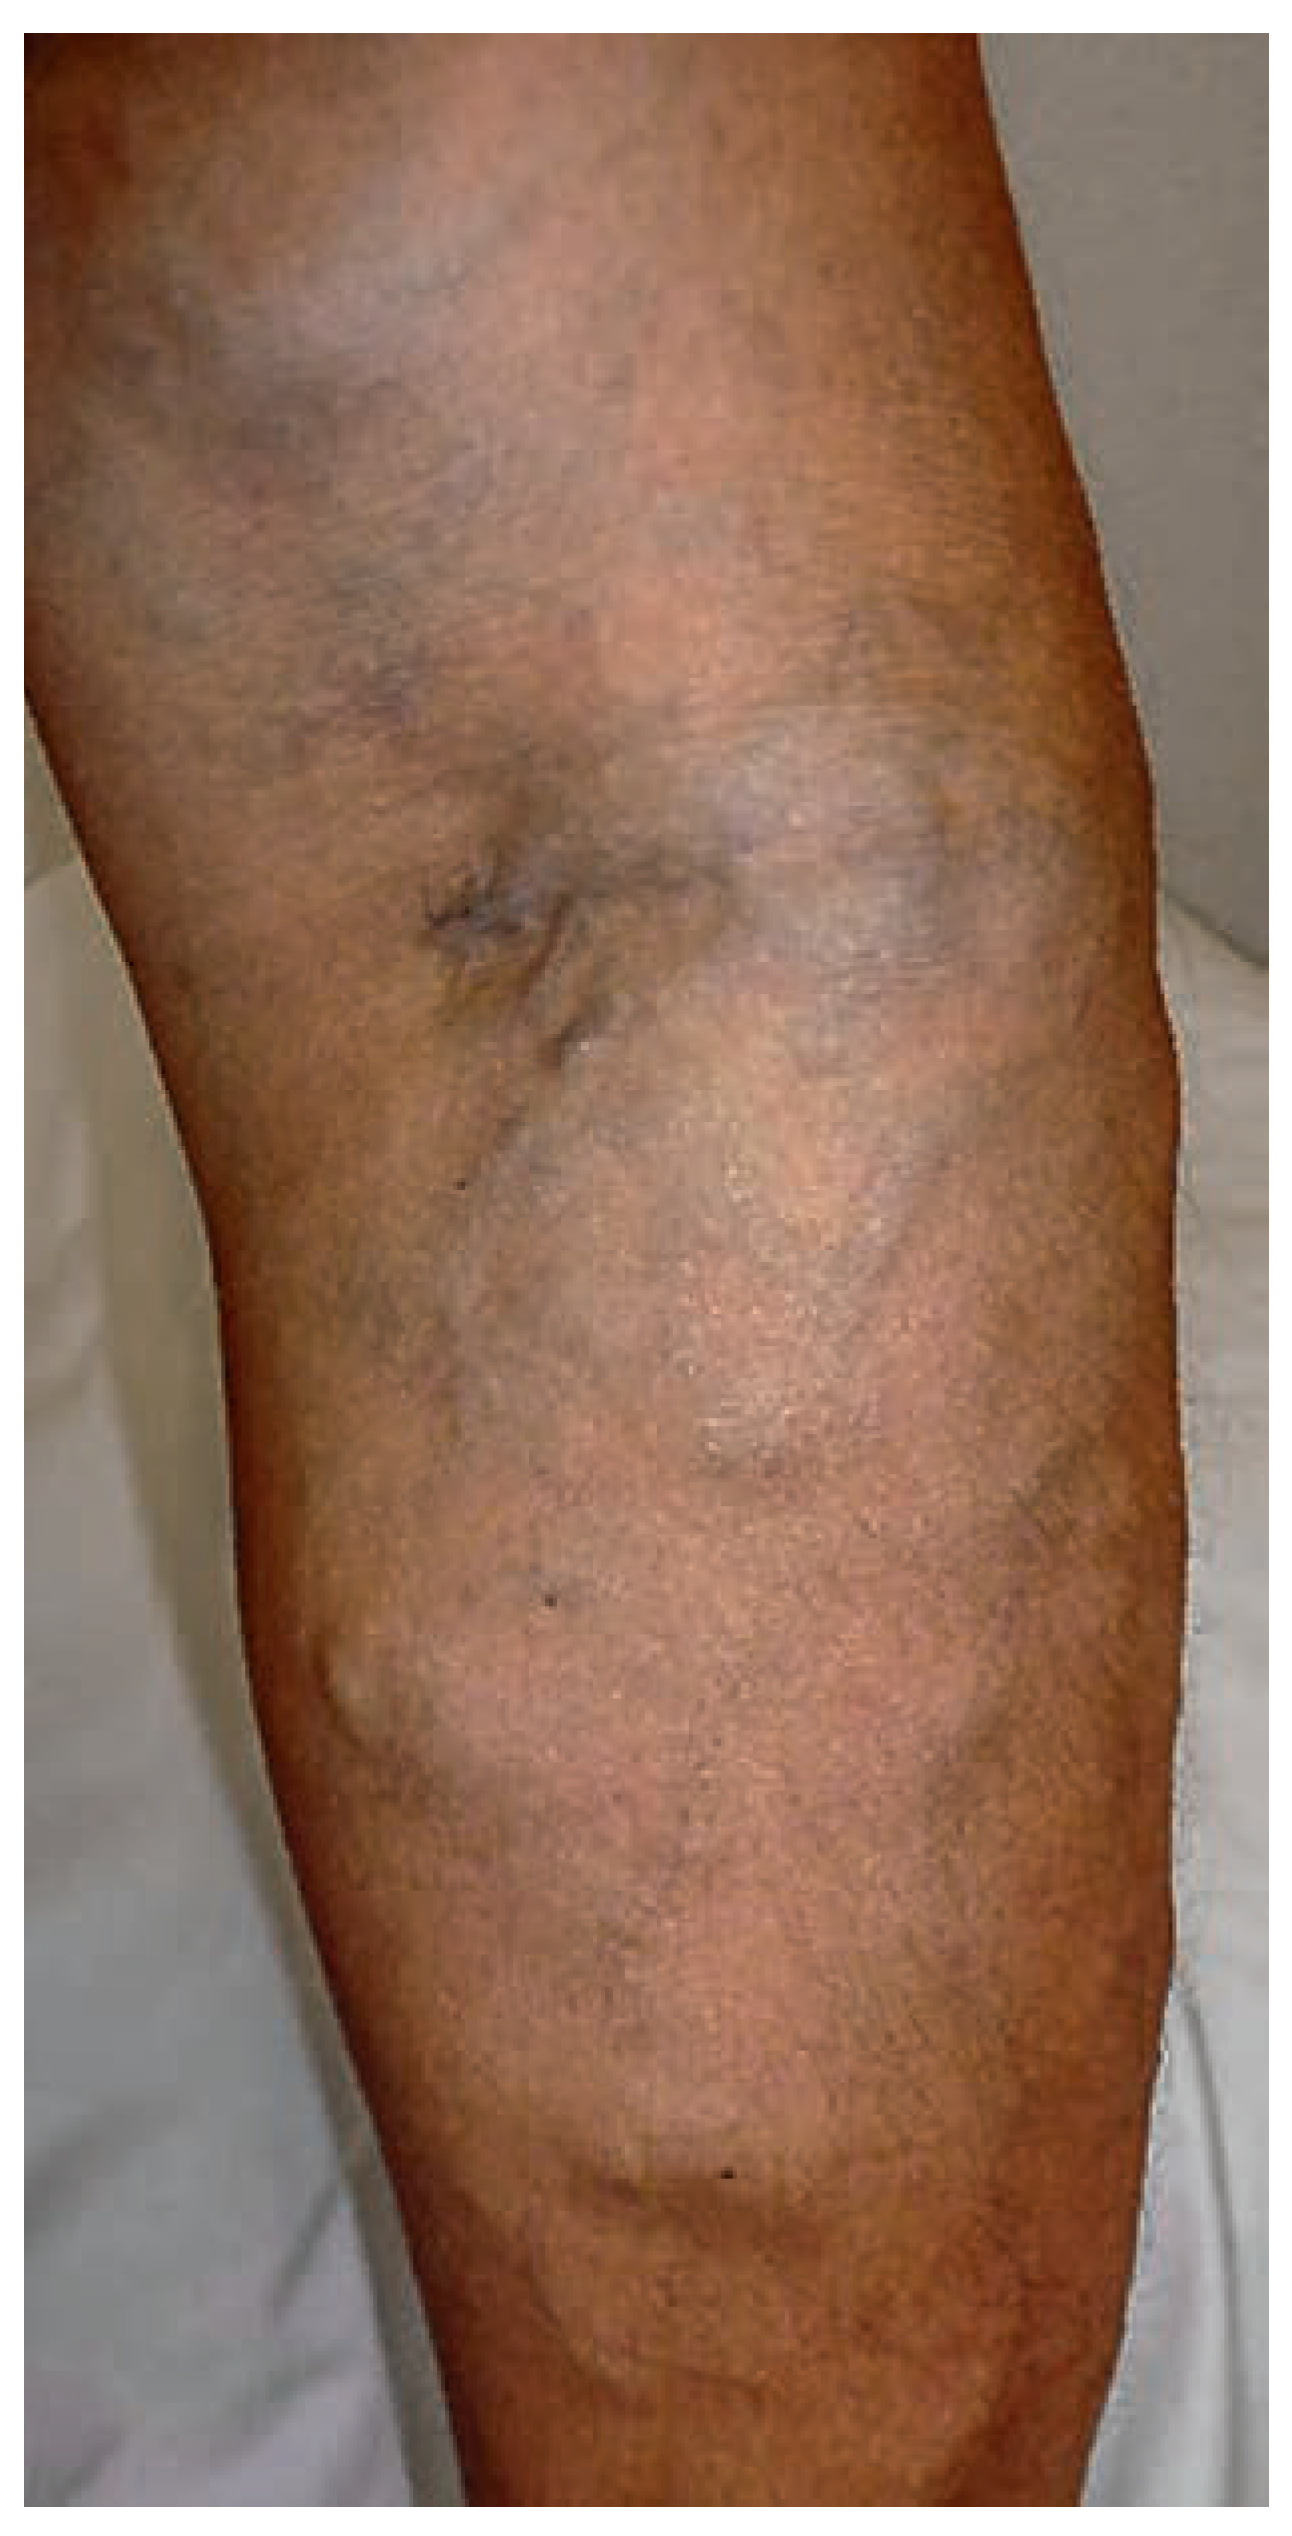

Venöse Malformationen